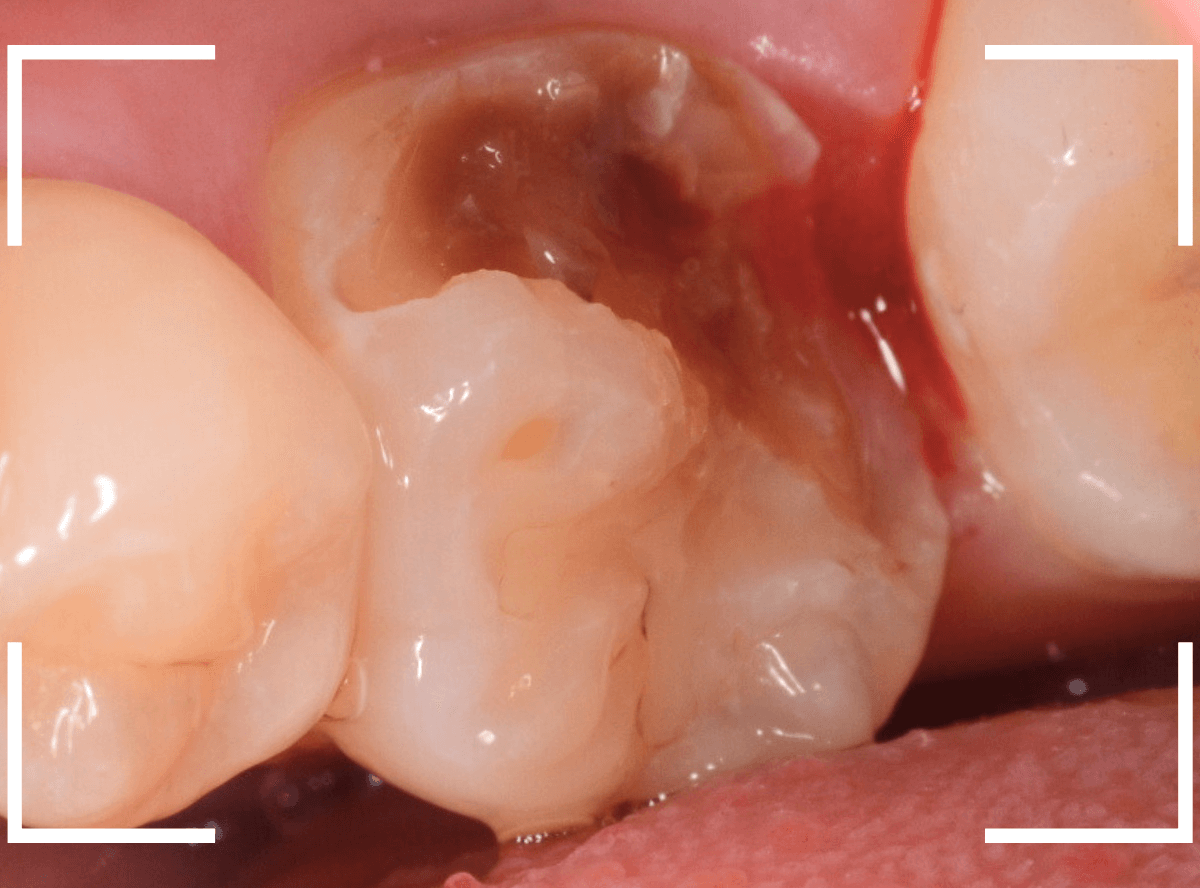

慎重に全ての虫歯を除去したところです。

〇部が神経の入り口が見えているところです。

神経を保護する処置をして、しばらく経過観察しますが、痛みが出て神経を除去する必要が出る可能性も高いです。

痛みが出ませんように・・・。